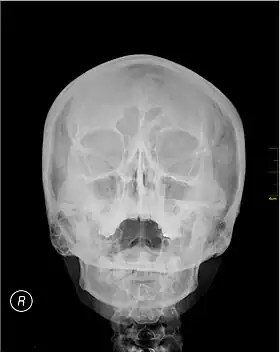

![]() A Waters' view radiograph showing the paranasal sinuses | |

Waters' view (also known as the occipitomental view) is a radiographic view of the skull. It is commonly used to get a better view of the maxillary sinuses. An x-ray beam is angled at 45° to the orbitomeatal line. The rays pass from behind the head and are perpendicular to the radiographic plate. Another variation of the waters places the orbitomeatal line at a 37° angle to the image receptor. It is named after the American radiologist Charles Alexander Waters.

Waters' view can be used to best visualise a number of structures in the skull.

- Maxillary sinuses.

- Frontal sinuses, seen with an oblique view.

- Ethmoidal cells.

- Sphenoid sinus, seen through the open mouth.

- Odontoid process, where if it is just below the mentum, it confirms adequate extension of the head.